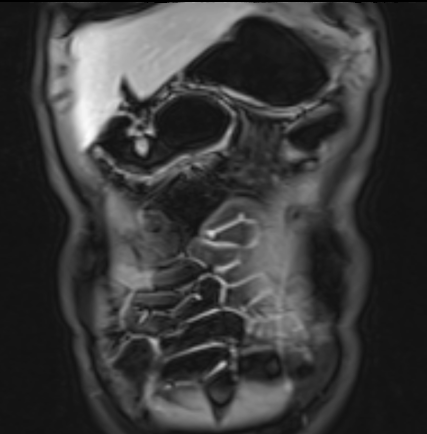

Bệnh nhân nữ 48 tuổi, đang điều trị bằng thuốc kháng TNF, được chỉ định nội soi đại tràng.

Phát hiện hẹp lòng ruột ở đại tràng sigma, không thể vượt qua được khi nội soi.

MR-enterography được thực hiện để đánh giá mức độ lan rộng của chỗ hẹp.

Ruột non bình thường, nhưng ghi nhận các đoạn hẹp ở đại tràng xuống và đại tràng ngang.

Cả hai đoạn hẹp đều có thành ruột dày đến 8 mm và ngấm thuốc rõ rệt theo kiểu niêm mạc ở đại tràng xuống và kiểu phân lớp ở đại tràng ngang.

Giãn ruột trước chỗ hẹp được ghi nhận ở cả hai đoạn.

Do các chỗ hẹp này không hiện diện khi nội soi đại tràng trước khi điều trị kháng TNF, nhiều khả năng chúng đã hình thành trong quá trình điều trị.

Do đó, quyết định phẫu thuật cắt đại tràng gần toàn bộ với miệng nối hồi-sigma đã được đưa ra.